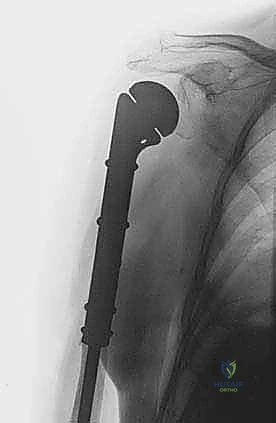

* المسمار النخاعي التشابكي (Intramedullary Nailing): يتم إدخال سيخ معدني قوي من التيتانيوم داخل التجويف النخاعي لعظم العضد بالكامل، وتثبيته بمسامير عرضية من الأعلى والأسفل. هذه الطريقة توفر دعماً ميكانيكياً هائلاً للعظم، وتمنع الكسر، وتسمح للمريض باستخدام ذراعه فوراً.

* غالباً ما يتم إجراء هذه الجراحة بتدخل محدود (Minimally Invasive) باستخدام أجهزة التنظير الإشعاعي (C-arm) داخل غرفة العمليات لضمان الدقة المطلوبة دون الحاجة لشق جراحي كبير.

إعادة البناء الميكانيكي: يتم إدخال المكونات المعدنية (سواء مسمار نخاعي، شرائح، أو مفصل صناعي) وتثبيتها بقوة باستخدام الإسمنت العظمي إذا لزم الأمر. يتم التأكد من ثبات الهيكل الجديد تحت جهاز الأشعة السينية المباشر (C-arm).